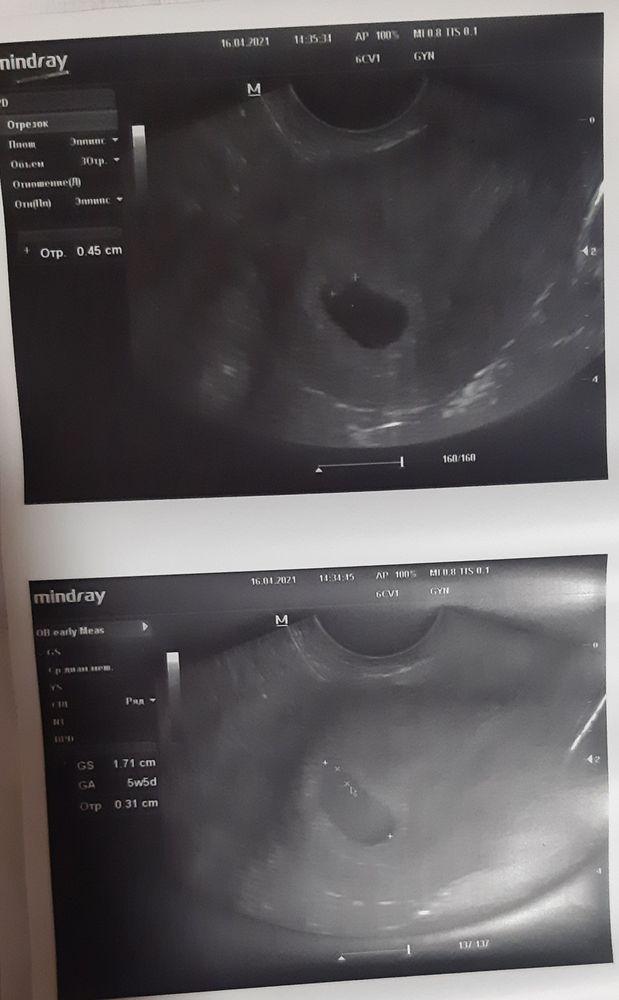

Я БЕРЕМЕННА !На 19 дпп пошла на узи чтобы посмотреть плодное яйцо, нашли, счастливая пошла домой🙂. На следующий день на 20дпп в обед обнаружила у себя кровь, чуть не посидела, сразу списалась с ре. все назначения сделала, крови больше не было и мазни тоже , ну и ждала 23дпп узи🥰. Ну и настал сегодняшний день ииии ттаааддаааммм

у нас все хорошо 🥰🥰🥰🥰. Какой же он маленький, но как сердечко стучит это неописуемо 🥰🥰🥰. Девочки идите к своей цели, знаю что тяжело, но это того стоит😘🤗. У нас ещё все впереди, но я верю в свою кроху🙏🤞. На всех чихаю заразно осторожно 🤗🤗😘😘🤧🤧🤧🤧🤧🤧.